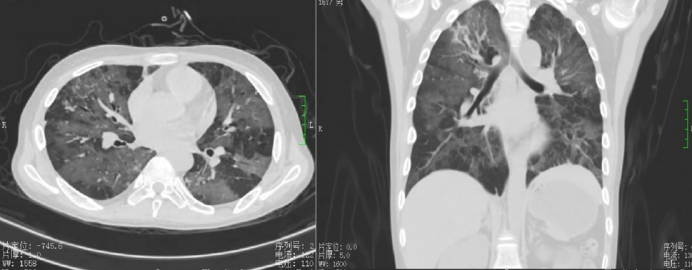

胸部CT示两肺纹理增粗紊乱;两肺各叶见多发斑片状、絮状、条索状密度增高影,边缘模糊,两肺呈“马赛克”改变(图2)。